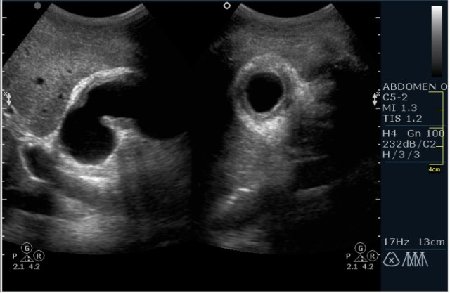

Мужчина 42 года; жалобы на периодические боли в эпигастрии. УЗИ области жёлчного пузыря выявило интересную картину; наблюдается фокальное утолщение стенок пузыря в области тела. Интересно узнать Ваше мнение?

В Желчном пузыре определялся мелкий конкремент и диффузное равномерное гипоэхогенное утолщение стенки на отграниченном участке, заключение морфологов-воспaлительный процесс (признаки холецистита).

Мне интерено, а почему Вы решили что это аденомиоматоз? На представленных сонограммах нет признаков этого заболевания, за исключением фокального утолщения стенки (что крайне не специфично, см. ниже). Если мы не находим пристеночных синусов (Ашоф -Ракитанского) образующихся за счёт неравномерной гиперплазии эпителия ЖП с протрузией эпителия в стенку, и не видим гиперэхогенные фокусы в стенке за счёт кристаллов холестерола; мы не можем выставлять диагноз аденомиоматоз. В нашем случае мы имеем дело с равномерным гипоэхогенным утолщением (см. сонограммы призведённые линейным датчиком с высоким разрешением).